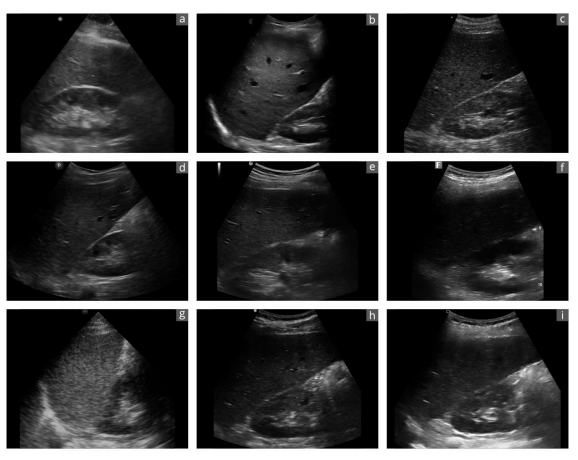

Figure 4. Exemplary sonographic images of a liver-kidney section from the same subject using different devices

?